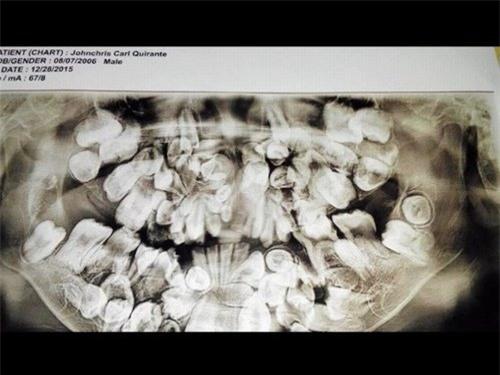

Phim chụp X-quang vòm miệng chi chít răng của John

soc: be trai 9 tuoi moc gan 300 chiec rang trong mieng hinh anh 1